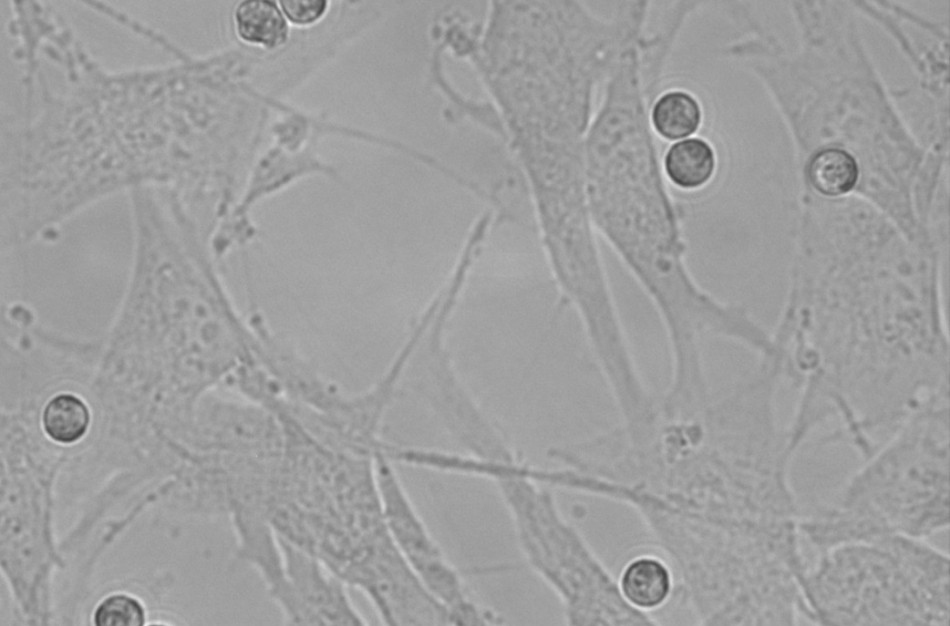

Viena svarbiausių pastarųjų metų sričių – eozinofilų potipių poveikis plaučių struktūrinėms ląstelėms – bronchų lygiųjų raumenų ląstelėms ir plaučių fibroblastams. Tyrimas buvo atliekamas kombinuotųjų kultūrų in vitro modelyje, vertinant eozinofilus, išskirtus iš skirtingais astmos fenotipais sergančių asmenų.

Pagrindinis mūsų tyrimo išskirtinumas – panaudotas kombinuotųjų ląstelių kultūrų modelis, kurio metu iš tiriamųjų asmenų kraujo išgryninti eozinofilai gali tiesiogiai kontaktuoti su in vitro auginamomis kvėpavimo takų struktūrinėmis ląstelėmis – bronchų lygiųjų raumenų ląstelėmis ir plaučių fibroblastais.

Eozinofilai – ląstelės, išskiriančios ypatingai didelį kiekį skirtingų citokinų, chemokinų, augimo veiksnių ir fermentų. Visų šių veiksnių svarba astmos metu neabejotina, tačiau tyrimų, kuriuose būtų vertinama tiesioginė eozinofilų įtaka kitoms ląstelėms po prisitvirtinimo ant jų paviršiaus – nėra.

Taikydami šį metodą, galime tiksliau atsakyti, kuriuose procesuose eozinofilai dalyvauja tiesiogiai, kur yra tik tarpininkai, ir ar jiems reikalingas grįžtamasis ryšys, papildoma aktyvacija iš kitų ląstelių“, – pasakojo LSMU MA Pulmonologijos klinikos Pulmonologijos laboratorijos mokslo darbuotojas, dr. Andrius Januškevičius.